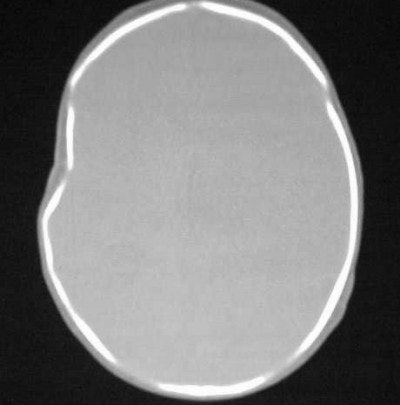

How about CT imaging for an in vitro trauma? Figure CT 5 is an axial image of a newborn child; there were no problems during the caesarian delivery. Two physicians and three nurses were present and the child was noted to have an indentation to the temporal region of the skull. Plain films were positive for a depressed skull fracture (Figure CT 6).

![]() |

| Figure CT 5 |

| Figure CT 6 |